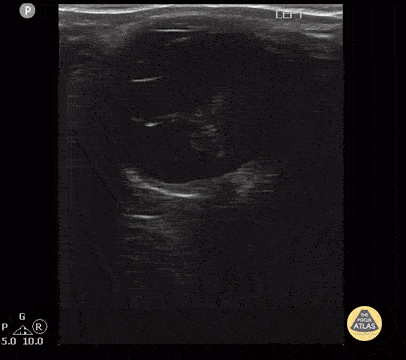

Peds-Orbital - Proliferative Vitreoretinopathy 2 of 2

19 year old with proliferative vitreoretinopathy (PVR) from a suspected chronic/older retinal detachment which had gone undiagnosed for a prolonged period of time. Contributor: Antonio Riera, MD